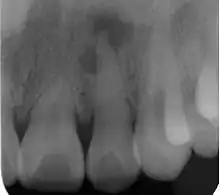

| Radiograph (X-ray) showing microdontia. Note also periapical lesion on the maxillary left lateral incisor. | |

Localized microdontia is also termed focal, or pseudo-microdontia. A single tooth is smaller than normal.[3] Localized microdontia is far more common than generalized microdontia,[2] and is often associated with hypodontia (reduced number of teeth).[1] The most commonly involved tooth in localized microdontia is the maxillary lateral incisor, which may also be shaped like an inverted cone (a "peg lateral").[3] Peg laterals typically occur on both sides,[2] and have short roots.[2] Inheritance may be involved,[2] and the frequency of microdontia in the upper laterals is just under 1%.[1] The second most commonly involved tooth is the maxillary third molars,[3] and after this supernumerary teeth.[3]